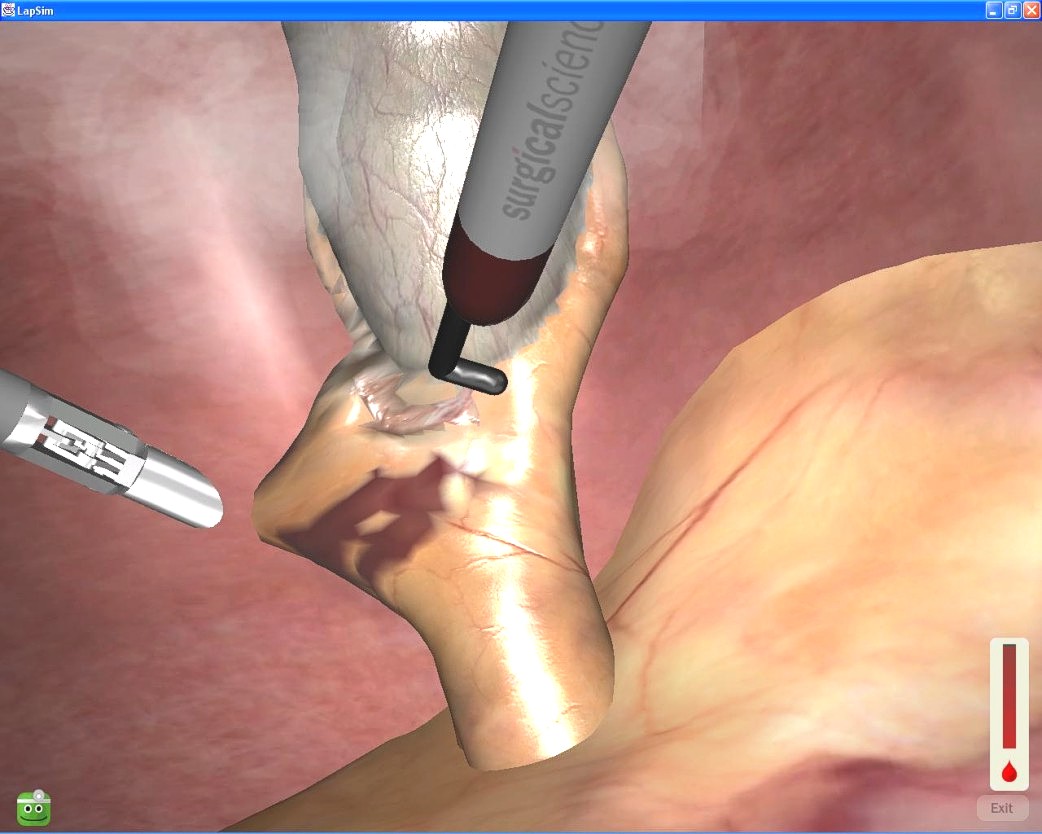

虚拟现实技术在医疗领域的应用

斯基普·里佐博士(Dr. Skip Rizzo)(右)正在使用虚拟现实沉浸疗法,监测创伤后应激障碍患者的治疗情况

南加州大学创新技术研究所的艾伯特•里佐博士(Dr. Albert Rizzo)回忆说,上世纪90年代,他帮助一位脑损伤患者进行康复治疗,患者很难保持激情配合治疗,但玩起掌上游戏俄罗斯方块的时候,却能一直全神贯注,由此他获得灵感,开始研究数字治疗方案。接下来的数年时间里,Rizzo与计算机科学领域的同事们合作研究,试图弄清楚虚拟现实下进行的模拟训练能否映射到三次元,对真实世界产生作用。为了探索这个问题,Rizzo花费了将近二十年,最终证明答案是肯定的。

Rizzo当年采用的虚拟现实技术不仅价格昂贵,信服力也不够。根据他的回忆,他的第一套虚拟现实系统Immersadesk 3D投影系统价格高达12.5万美元,第一套头戴式显示器当时售价1万美元,屏幕分辨率还只有640*480,同时还需要价格昂贵的SGI工作站来进行比较粗糙的头部动作跟踪以及高仿真的3D建模。

让人惊讶的是,即便是早期针对虚拟现实的尝试也证明这项技术完全可以为那些创伤后应激障碍(PTSD)等患者提供一个“真实”的治疗环境,Rizzo曾在1998年通过虚拟现实技术模拟出一个越南战争现场,植物啊、直升机啊等等标志物模拟得都相当粗略,当那个越南老兵从这个现场中走过一遭之后,他问:“比尔,你看到了什么?”,然后对方回答说:“我看到了稻田、丛林里的越南大兵还有一头水牛。”他看到的那些东西其实并不是模拟出来的,他们用自己的记忆填补了这些空白,然后感觉模拟现场就像真实场景一样。

即便科技发展到现在,模拟场景的虚拟疗法在真实度上也难以与真实世界中的沉浸疗法相媲美,但至少在治疗普通恐惧症和深度焦虑症方面,虚拟沉浸疗法确确实实是有效的。虚拟现实疗法公司Virtually Better的临床心理学家和培训主任马拉特•萨诺夫(Marat Zanov)指出,数百例临床研究显示,虚拟疗法在效果上完全不亚于现实疗法。

Virtually Better公司的暴风雨环境模拟治疗场景

大多数人对于虚拟现实的认知,仅仅停留在五感中的视觉、听觉两个感官上,但在医疗领域,研究人员多年来一直利用其他感官。

Virtually Better的临床医生将一种叫做“触觉震动台(vibrotactile platform)”的设备,使用到模拟环境中。这个平台的振动可以用在飞行模拟中,模拟喷射发动机的轰鸣,或是暴风雨中房子摇摇欲坠的感觉。“那些经历过真实龙卷风的人告诉我们,模拟环境中的触觉听觉简直太逼真了。”Zanov说道:“他们看着头盔显示器里显示的场景,听着那些模拟的声音,会惊叹说他们就好像回到了曾经历的飓风中。”

Virtually Better还在使用一种嗅觉机器“通过选择需要的气味”把患者带入创伤事件的记忆中。这些味道种类繁多,从车祸现场汽油燃烧的味道,到中东市场的香料气味,在戒除酒瘾烟瘾的模拟场景中,还能是烟酒的味道。

Zanov对此表示,模拟场景中,提供的感觉输入越多,就越有效。我们还从第六感下手。我们让患者沉浸在这个虚拟环境中,所有这些“虚拟”都是把患者重新置于引起他们恐慌的环境中去,以便我们更好地了解他们的情绪,这是治疗的关键。”

虚拟现实疗法较之现实中的情景暴露疗法通常更加方便和(或)低成本。“想想我们那些创伤后应激障碍的退伍军人,”Zanov说:“我们不可能真的把他们带回阿富汗或者伊拉克的交火现场。在过去,我们会让这些老兵通过想象,在脑海中唤回创伤事件的记忆,感觉好像又回到了当时。这个手法很棒,但对心理治疗师要求太高,需要花费太多时间和努力,并且有些病人就是缺乏想象力。但是通过虚拟现实技术,我们能让他们更快地进入到更逼真的场景中去。”

Zanov还指出,针对某些病症,虚拟现实技术还能够有效节约治疗成本,比如飞行恐惧症。在以前,使用情景暴露疗法的病人可能需要购买两人份的往返机票——一张给病人,另一张给医生。这样昂贵的飞行体验,或许要反复上5-10次,“但如果是使用虚拟环境,昂贵的机票钱果断可以省掉了。”

经过几十年的研究,研究人员已经证明了虚拟沉浸疗法的临床价值,与此同时,虚拟现实技术的新一波热潮则把这一概念从学术研究领域推广到实用领域,更好地服务于广大医患。

“现在的形势是,我们降低了成本,让普通治疗师也可以负担得起,”Virtually Better的首席执行官迈克尔·雅各布森(Michael Jacobson)说:“直到去年为止,它更多的是一种研究工具,而不是临床实操工具。它不方便,也不好用,并且相当烧钱。不过刚刚提到的Oculus改变了这一现状,让这一技术的实用性获得突破,而价格则走下神坛。现在我们看到越来越多的行业和个人开始对虚拟现实技术进行探索,过去人们只是在研究它,现在人们开始使用它。”

里佐也认为,随着以Oculus Rift为首的各色物美价廉的头戴式显示器的普及,在科技水平上,虚拟现实疗法已经具备了从理论到实战的可行性。里佐回忆说2004年他曾试图在注意力缺失症的治疗中采用虚拟现实疗法,“但是当时那些心理学专家对此并不看好,他们认为这种疗法过于复杂,不具备实际操作性,最主要的是他们根本不了解这项疗法,并且不愿支付2000美元的费用。”

然而现如今Rizzo在心理学大会上提到类似的虚拟现实疗法时,情况却发生了180度大转折。他说道:“我不必再把一半的演讲时间花费在科普什么是虚拟现实技术,去说服人们这并不是科幻小说中才会出现的技术。现在许多人们都已经开始了解这项技术,我完全可以单刀直入。”